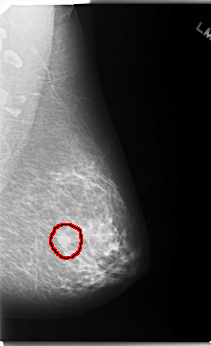

FILE: C_0124_1.LEFT_MLO.OVERLAY

TOTAL_ABNORMALITIES 1

ABNORMALITY 1

LESION_TYPE MASS SHAPE OVAL MARGINS MICROLOBULATED

ASSESSMENT 4

SUBTLETY 5

PATHOLOGY MALIGNANT

TOTAL_OUTLINES 1

BOUNDARY